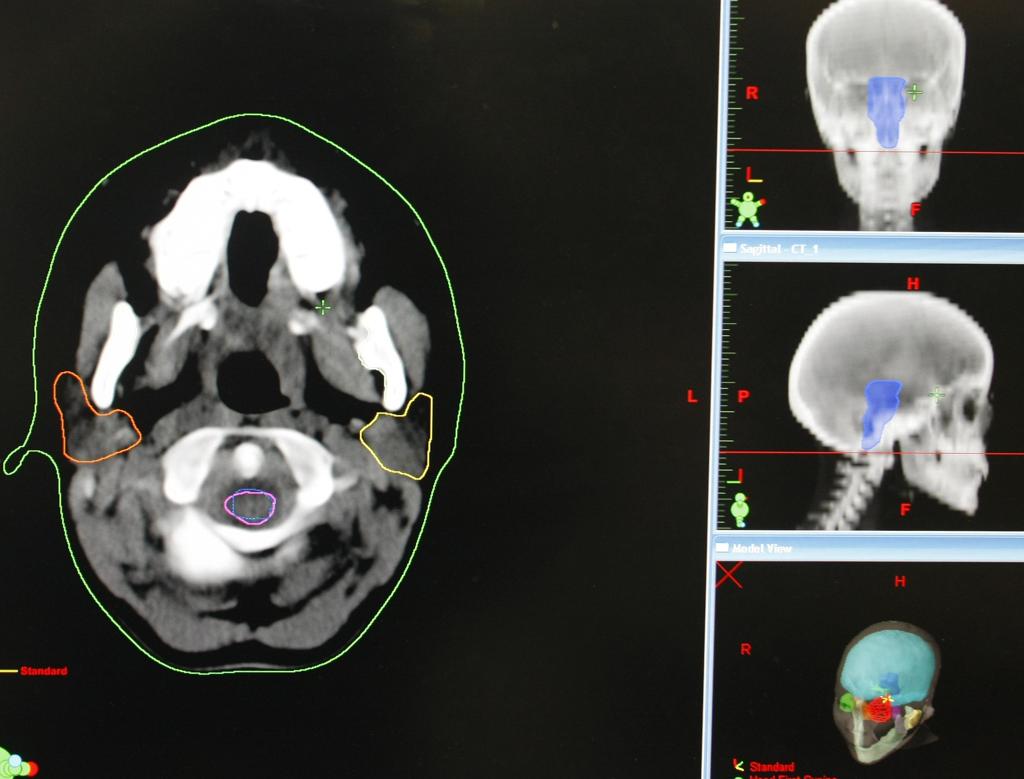

A Tomografia por Emissão de Pósitrons (PET, na sigla em inglês) passou a ser incluída no Sistema Único de Saúde (SUS) em abril de 2014 para diagnóstico de câncer de pulmão, colorretal e de linfomas.